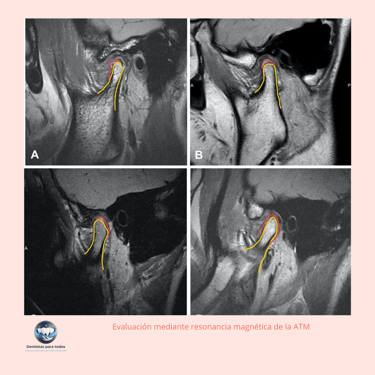

Evaluación Mediante Resonancia Magnética de la ATM

Importancia: La resonancia magnética (RM) es útil para evaluar los tejidos blandos de la ATM, incluyendo los discos articulares y los ligamentos, proporcionando información detallada sobre el estado de la articulación.

Escaneo: La máquina de resonancia magnética realiza un escaneo detallado de la ATM, capturando imágenes de alta resolución de los tejidos blandos.